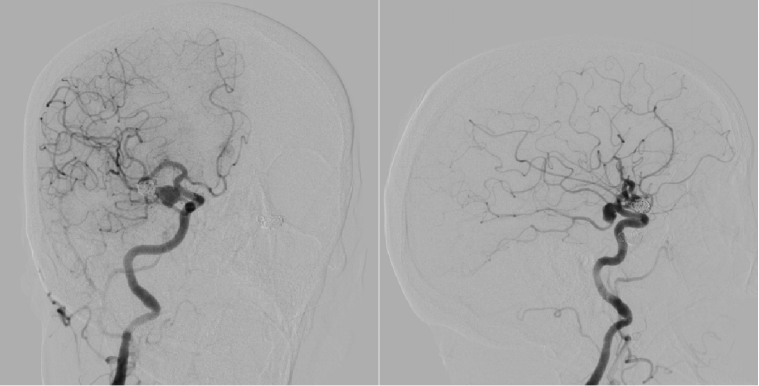

Preoperative Evaluation

Preoperative angiography revealed a shared trunk of bilateral anterior cerebral arteries, with a saccular aneurysm (8 mm × 6 mm) on the left anterior cerebral artery, a recurrent aneurysm (9 mm × 5 mm) on the left middle cerebral artery, and a wide-neck aneurysm (8 mm × 8 mm) on the right posterior communicating artery.

3D imaging of the left internal carotid artery

Anterior-Posterior view of the left internal carotid artery

Angiography of the right internal carotid artery

Considering the patient’s vascular condition, aneurysm size, location, and morphology, Dr. Lobelo’s team decided to first treat the distal left middle cerebral recurrent aneurysm and the left anterior cerebral saccular aneurysm, followed by treatment of the proximal right posterior communicating wide-neck aneurysm.